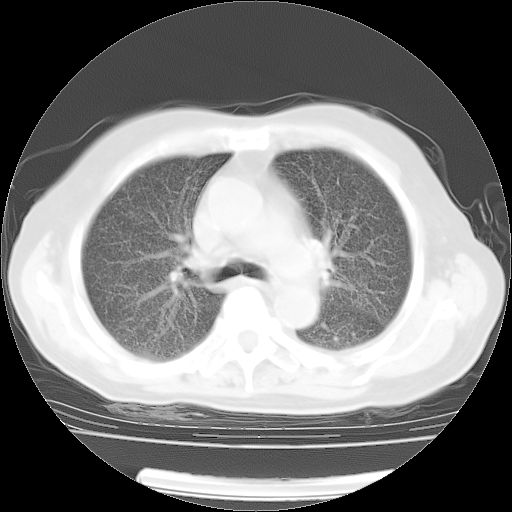

4月14日肺部CT

楼主| 发表于 2010-4-28 16:51 | 显示全部楼层

楼主| 发表于 2010-4-28 16:53 | 显示全部楼层

肺部CT平扫未见异常。